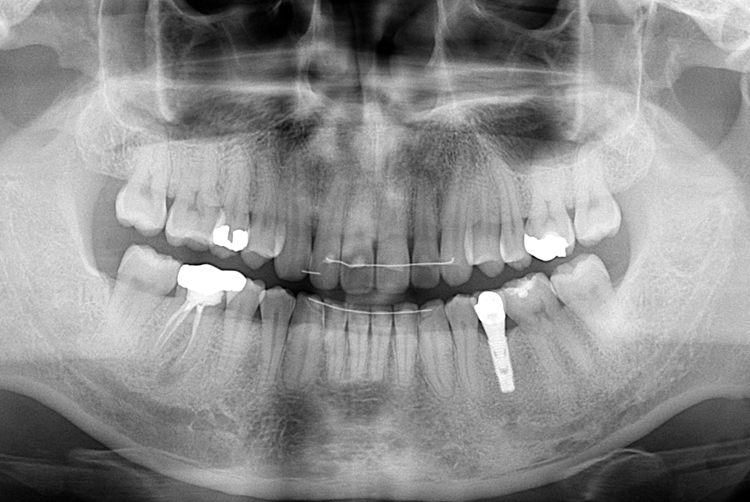

[임플란트] 어금니 임플란트

치료전 : 2018-06-06